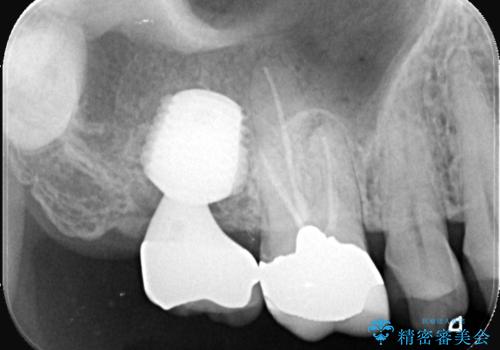

根尖性歯周炎|歯根嚢胞|インプラント治療

- 治療計画

- 右上7番に瘻孔を認め、根管治療を実施しましたが、瘻孔が再発し治癒が得られなかったため、抜歯のうえインプラントによる補綴治療を行いました。

抜歯と歯根嚢胞の除去を行った後、インプラントで治療しました。治療後は「自分の歯のように咬める」と大変ご満足いただけました。